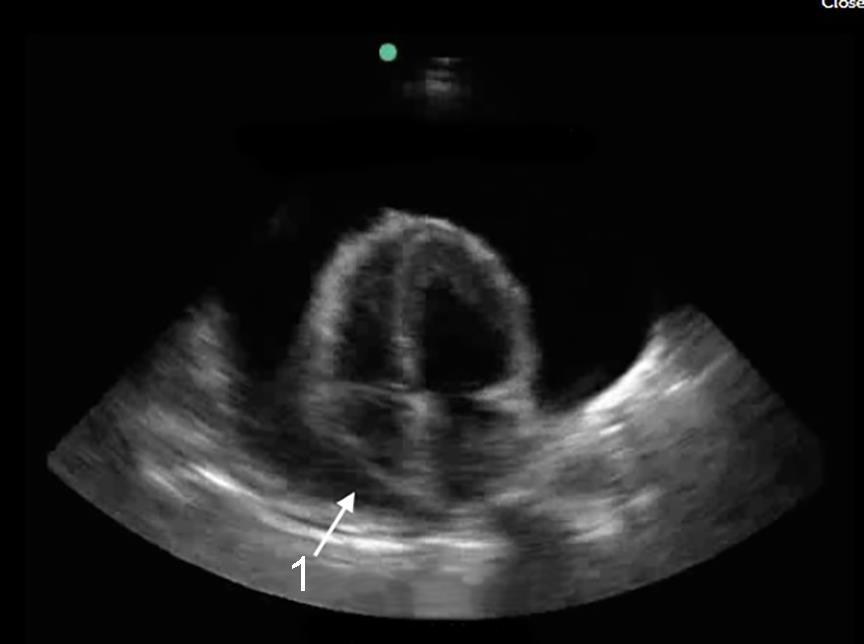

心尖 4 腔心包填塞图像

右心房舒张期塌陷 (RA)